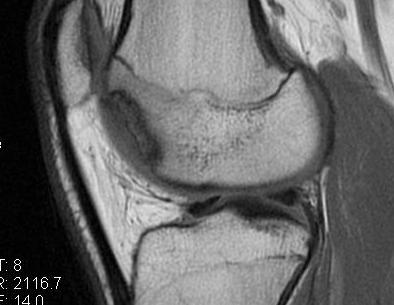

MFC OCD on presentation T2 image 6 months later

T1 sagittal on presentation T1 sagittal six months later